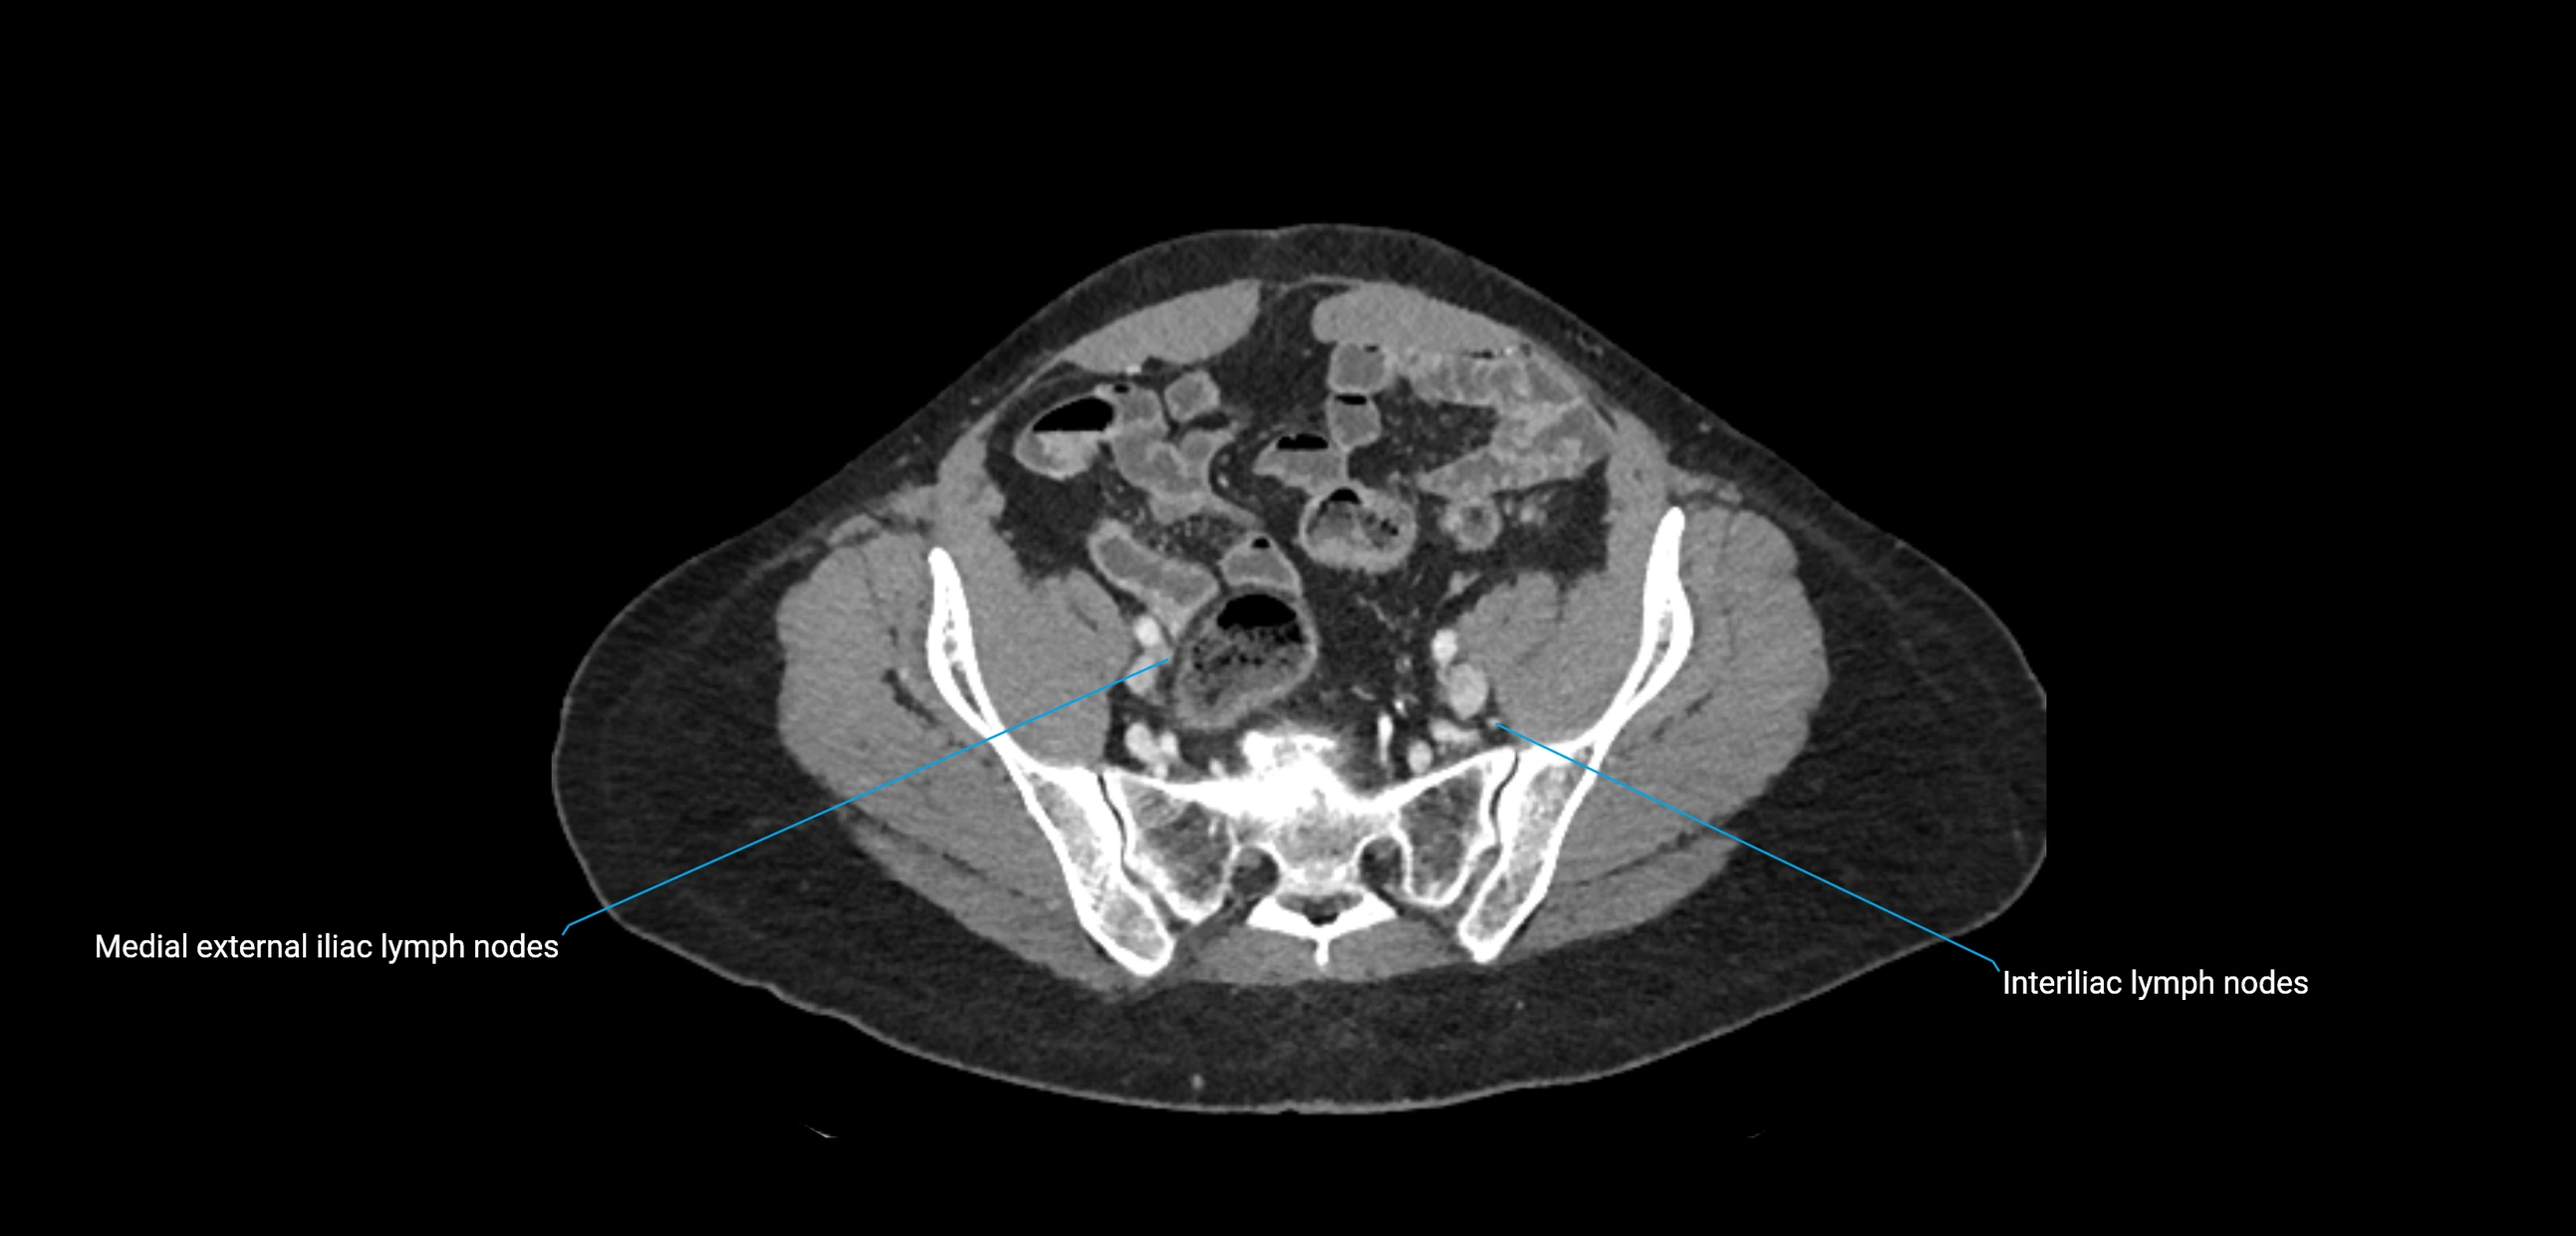

MRI images

image